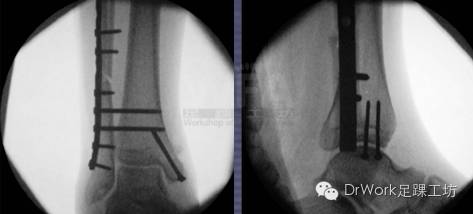

• 术中复位后正位片、侧位片与健侧对比